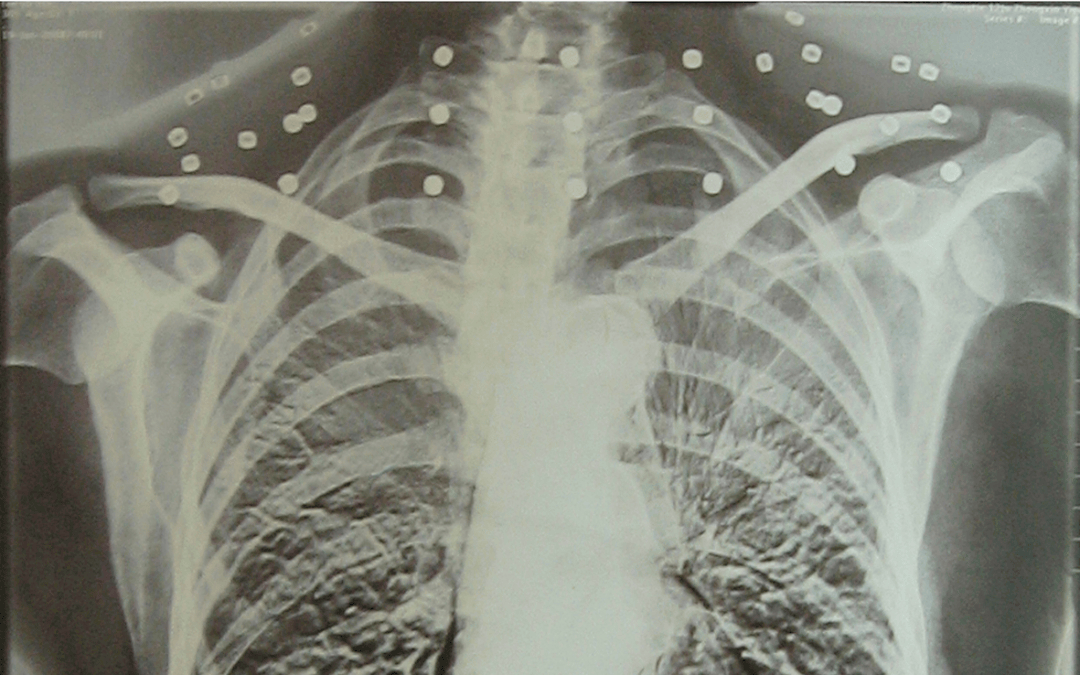

这张照片

是今年82岁的吴以先老人

拍摄的一张CT照

但实际上是

吴以先的颈部和腹部

共分布着33枚弹片

他体内的弹片都没有取出

身体留有弹片的位置就有痛感

但吴以先不考虑取出弹片

在他看来

这是他与战友并肩作战的见证

是他的勋章